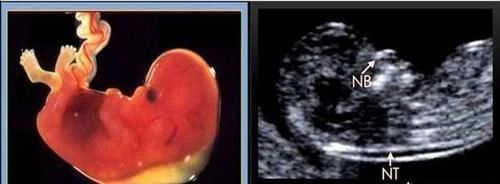

【 鼻骨|孕23周+2四维显示无鼻骨,做唐筛NT低风险,孩子能留吗?】(图片来自网络)

孕23周+2四维显示无鼻骨,做唐筛NT低风险,孩子能留吗?对于正常的胎宝宝来说,他们是有两块鼻骨的,在出生以后,两块鼻骨会逐渐的融合到一块,而胎宝宝的鼻骨通常在怀孕6周的时候就开始发育了,到了怀孕10周左右,胎宝宝的面部的骨骼部分开始骨化,所以在做NT检查的时候,胎宝宝已经能够看到鼻骨了,如果之后的四维彩超闲适胎宝宝鼻骨不清楚的话,孕妈妈们可以对照一下自己的NT检查,如果没有鼻骨,在NT检查的时候就会写出来的。